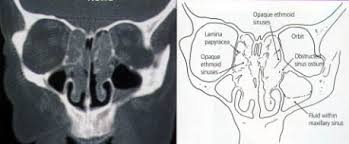

Normally these spaces are fairly open, but nasal polyps can grow large enough to block them. Urethral secretions are normal physiological like saliva in mouth whose role is to keep urethra moist when they are secreted excess they peep out as sticky fluid this excessive secretions most common. Epidemiology it is most commonly encountered in adults and rare in children. Nasal polyps are abnormal growths inside the nasal cavity or paranasal sinuses. Learn about causes, risks, home remedies, and.

They can make your nose feel stuffy, and can decrease your sense of smell. These have been subdivided into 4 stages. They're not usually serious, but they can keep growing and block your nose if not treated. Nasal polyps are polypoidal masses arising mainly from the mucous membranes of the nose and paranasal sinuses. Nasal polyps can grow anywhere on the lining of the nose or the sinuses.

Sinonasal polyposis refers to the presence of multiple benign polyps in the nasal cavity and paranasal sinuses. Read about the symptoms, causes, treatments and when to see a gp. Nasal polyps are polypoidal masses arising mainly from the mucous membranes of the nose and paranasal sinuses. They often grow where the sinuses open into the nasal cavity. Nasal polyps usually grow in the shape of a teardrop. Nasal polyps are soft, painless growths inside the nasal passages. Large polyps may cause difficulty breathing, infections, and an altered sense of smell. It is not a neoplasm.

I have tryed so many things please 0763543975. A polyp is an abnormal growth that arises from tissues in the mucous membrane. Larger ones can block normal drainage from the sinuses. In advanced cases, polyp may be seen hanging. A nasal polyp is a benign (noncancerous) tumor that grows from the lining of the nose or sinuses. Symptoms include trouble breathing through the nose, loss of smell, decreased taste, post nasal drip, and a runny nose. Read about the symptoms, causes, treatments and when to see a gp. A modification of this system includes one more stage i.e. I have nasal polyps may any one who can help me please. Small nasal polyps may not cause symptoms. Polyps are the most common expansile lesions of the nas. Nasal polyps usually grow in the shape of a teardrop. The majority of people with nasal polyps will experience nasal congestion, which may be severe and unable to be helped by typical allergy medications.